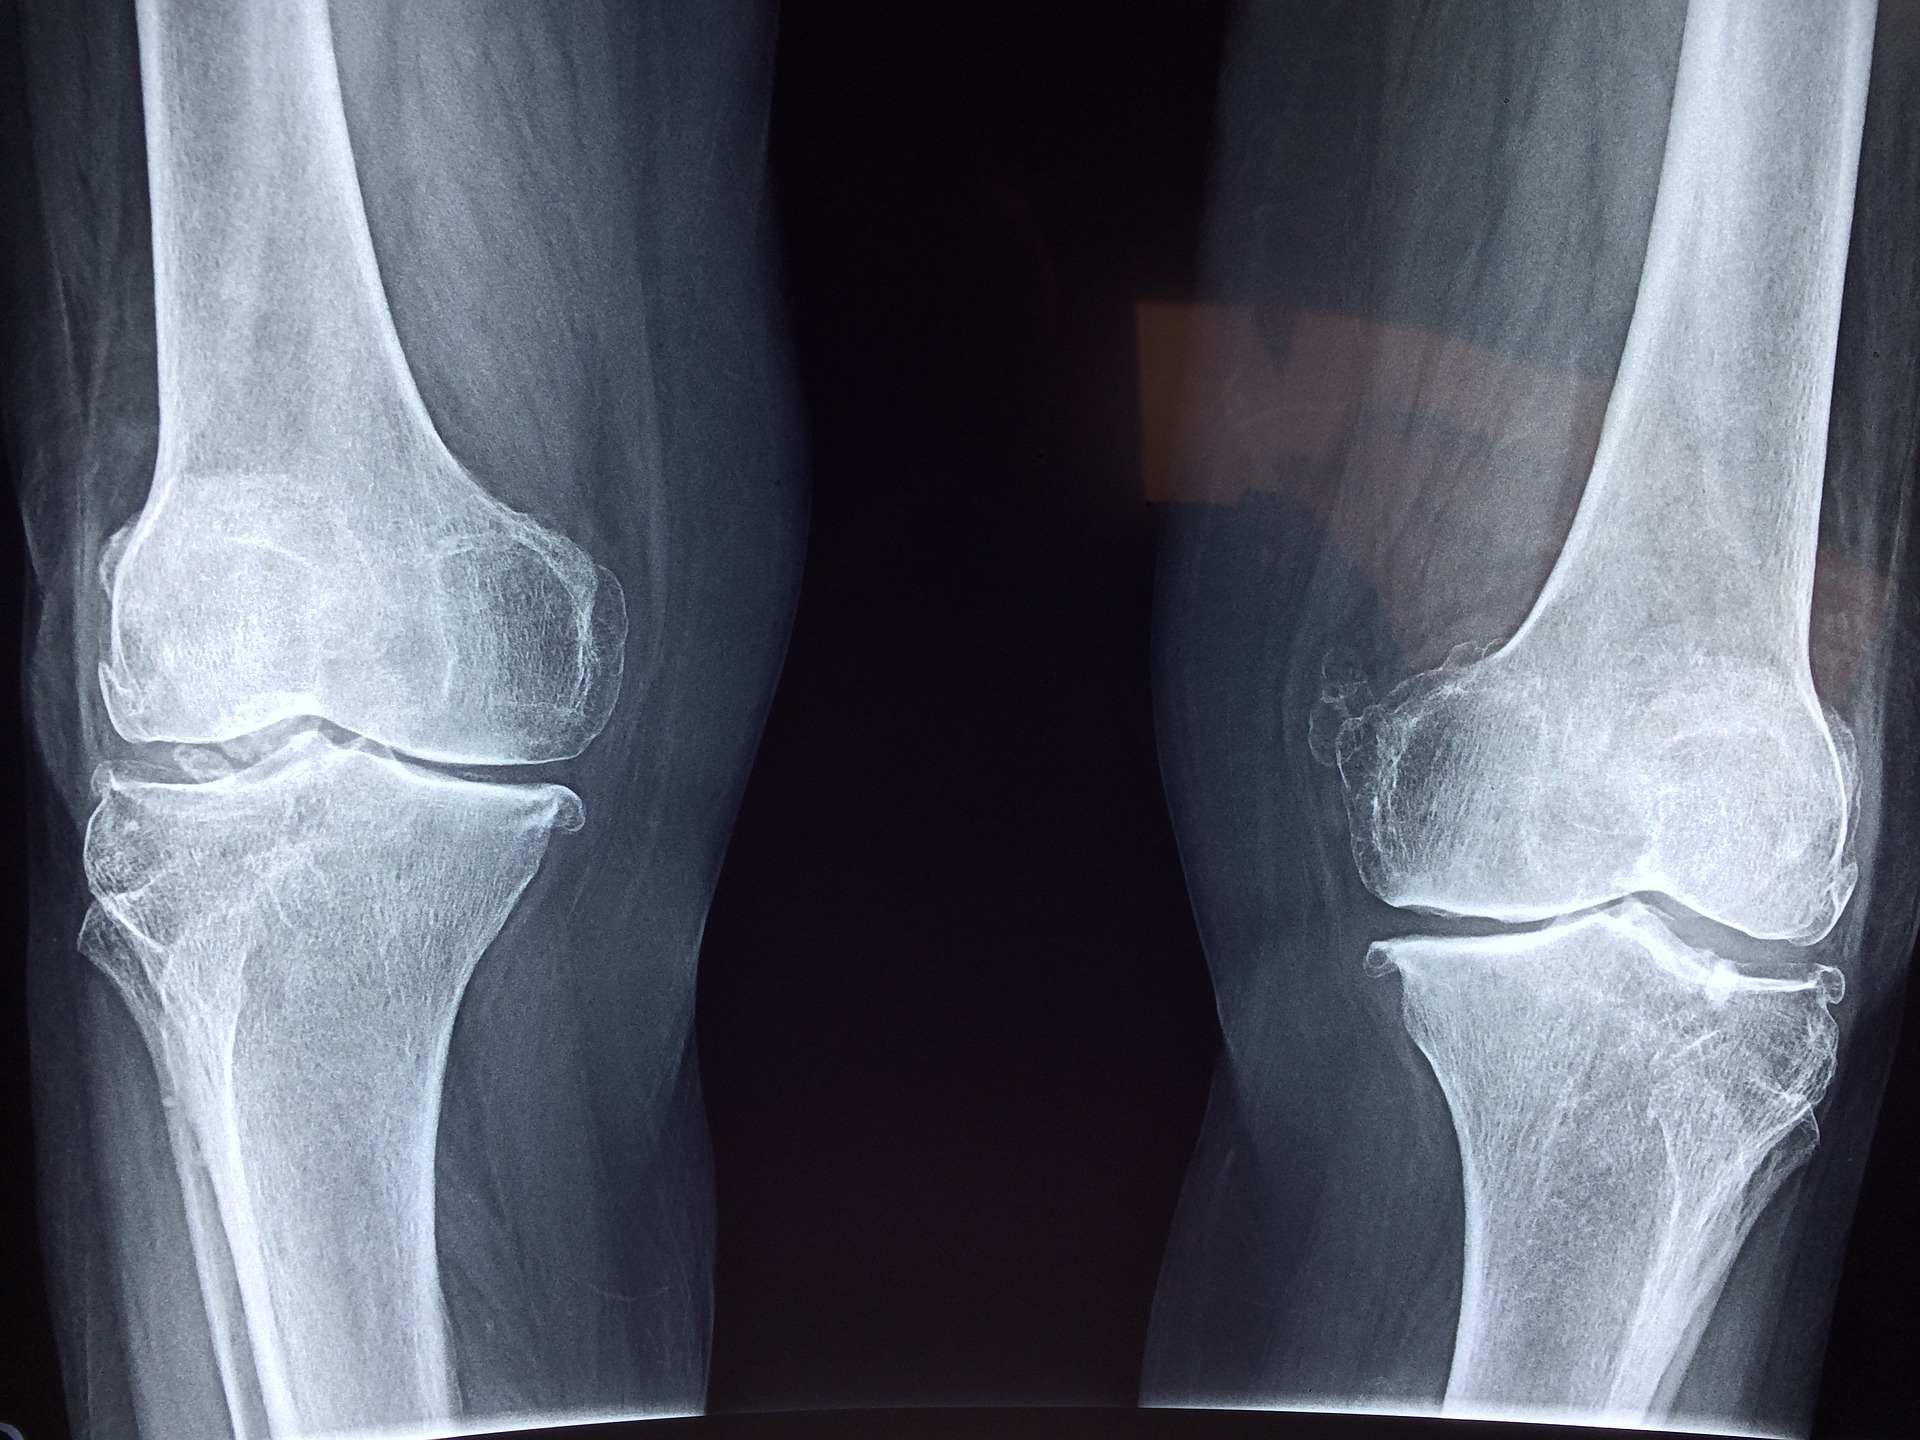

골다공증은 뼛속에 구멍이 많다는 뜻으로 뼈의 양이 감소하여 강도가 약해져 골절이 발생하기 쉬운 상태를 말합니다. 우리 몸속의 뼈는 지속적으로 교체되는데, 원래 있던 낡은 뼈가 소실되는 과정을 골흡수, 새로운 뼈가 만들어져 교체되는 과정을 골형성이라고 합니다. 이때 골형성보다 골흡수 과정이 많아지면 뼈의 양이 줄어들어 골밀도가 급격히 떨어지는 골다공증이 발생하게 됩니다. 골다공증은 크게 두 가지로 분류됩니다. 일차성 골다공증은 폐경 후 또는 노년기 골다공증을 말하는 것으로 특별한 원인 질환 없이 일어납니다. 이차성 골다공증은 특정 질환이나 약제 등에 의해 유발됩니다. 통계에 의하면 일차성 골다공증 중 폐경 후 골다공증을 겪는 환자들이 가장 많은 것으로 나타났습니다. 즉 골다공증은 주로 중·노년층 여성에게서 많이 발생하는데 이는 폐경으로 인해 급격히 줄어든 여성호르몬과 관련이 있습니다. 골다공증은 초기에는 별다른 징후를 보이지 않는 것이 특징입니다. 이 때문에 '소리없는 뼈도둑'이라고 불리기도 합니다.

골다공증은 초기에는 특별한 증상을 보이지 않는 것이 특징입니다. 그러다 뼈가 점차 약화되면서 골절이 일어나면 그 후에 발견되는 경우가 많습니다. 초기에 척추 주위 통증을 호소하는 경우도 있는데 이는 척추의 변형이나 압박 골절로 진행되어 극심한 통증과 함께 허리나 등이 구부러지고 신장이 줄어드는 증상이 나타납니다. 또한 골다공증은 골절의 위험을 증가 시킵니다. 골다공증이 진행되면 뼈가 약해져 일상생활에서 일어나는 작은 충격만으로도 뼈가 부러질 수 있습니다. 골절은 어느 부위에서든 발생할 수 있지만 흔히 발생하는 부위는 손목, 고관절, 대퇴골 상부 등으로 연세가 많은 환자의 경우 미끄러져 넘어지지 않도록 주의해야 합니다. 골절이 일어난 이후에는 만성적인 통증이 생기거나 재골절이 일어날 가능성이 높습니다. 실제로 골다공증 환자의 25% 정도가 재골절을 경험하는 것으로 보고되며, 첫 골절에 비해 치료가 어려운 것으로 나타납니다. 또 고령층에서의 골절은 장기간의 침상생활로 이어져 합병증을 유발할 위험이 있습니다.